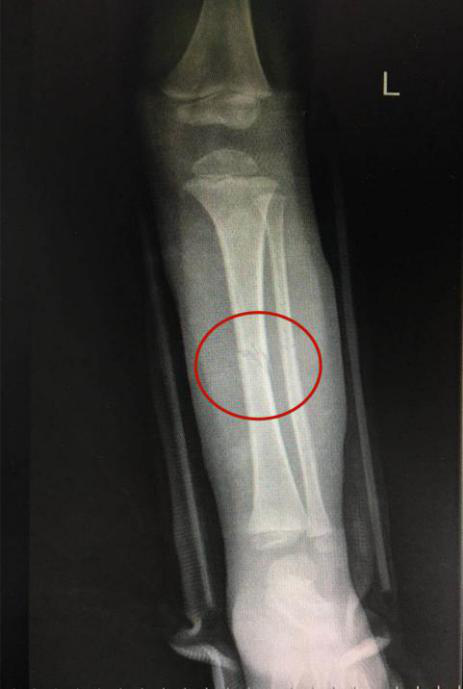

復位后,經(jīng)再次照X光顯示,患兒左下肢脛腓骨斷端緊密對合,外觀畸形得以糾正,手法復位治療非常成功。

手法復位后X片顯示脛腓骨斷端嚴密對合,左下肢中段畸形糾正